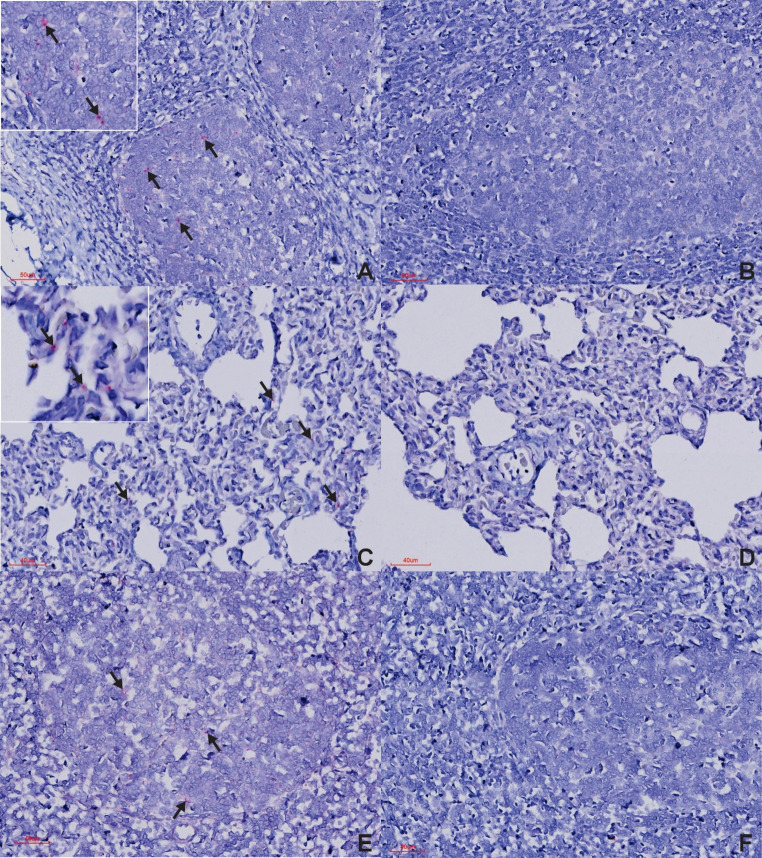

BaseScope™ in situ hybridisation (Advanced Cell Diagnostics, USA) was used to detect foot-and-mouth disease virus (FMDV), species Aphthovirus vesiculae, in formalin-fixed paraffin-embedded tissues from African buffalo (Syncerus caffer, n = 15) culled from the Kruger National Park - where the South African territories (SAT)-1, -2 and - 3 serotypes are endemic - as part of their population management program. Foot-and-mouth disease viral RNA was consistently detected in the palatine tonsils and lungs, demonstrating these as primary sites of viral persistence. Detection in the retropharyngeal lymph nodes and interdigital skin was less frequent, while oropharyngeal tissue showed rare positivity. Other sampled tissues - including the tip of the ear, eyelid, tongue, lip, and coronary band - proved suboptimal for identifying FMDV-positive buffalo or carriers. These findings highlight the value of BaseScope™ for detecting low viral loads of FMDV in persistently infected African buffalo, with a notable predilection for the palatine tonsils and lungs.

BaseScope™原位杂交技术(美国先进细胞诊断公司)用于检测从克鲁格国家公园(南非领土(SAT)-1、-2和- 3血清型流行的地方)采集的非洲水牛(Syncerus caffer, n = 15)的福尔马林固定石蜡包埋组织中发现的口蹄疫病毒(FMDV),即水疱型Aphthovirus vesiculae,作为其种群管理计划的一部分。在腭扁桃体和肺部持续检测到口蹄疫病毒RNA,表明这些是病毒持续存在的主要部位。在咽后淋巴结和指间皮肤的检测较少,而口咽组织显示罕见的阳性。其他取样组织——包括耳尖、眼睑、舌头、嘴唇和冠状动脉带——被证明不是确定口蹄疫阳性水牛或携带者的最佳方法。这些发现突出了BaseScope™在持续感染的非洲水牛中检测低病毒载量FMDV的价值,特别是对腭扁桃体和肺部的显著偏爱。